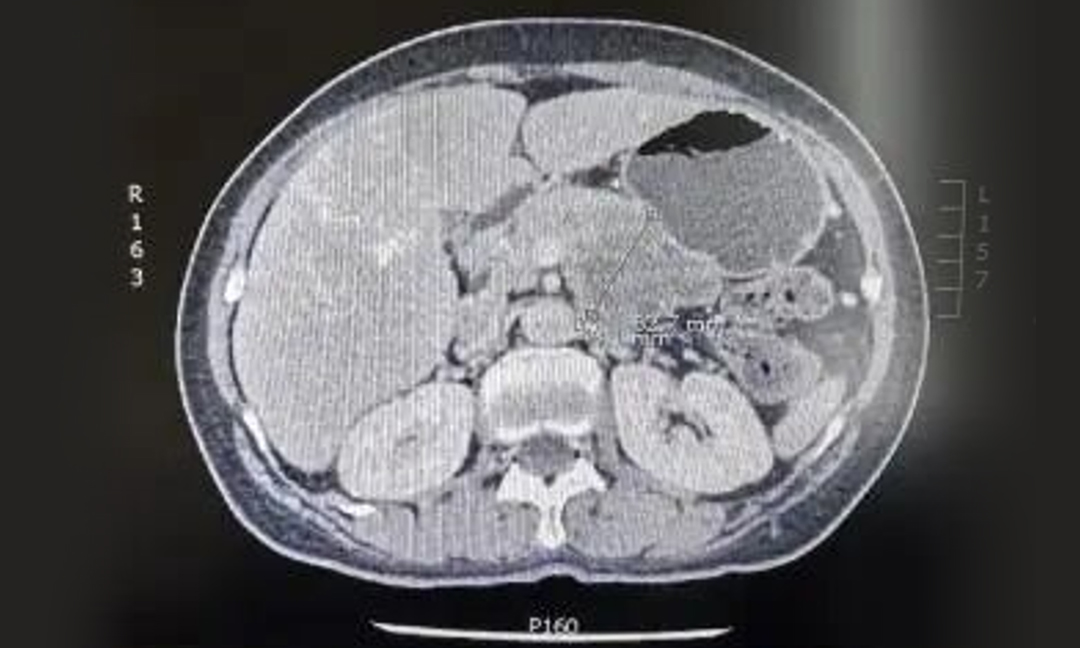

患者女,76岁,因食欲下降骤减和莫名乏力在当地医院进行检查。中上腹增强CT检查发现胰体尾部占位,较大截面范围约6.5cm ×4.6cm,穿刺活检病理提示:胰腺导管腺癌。

▲ CT显示胰体尾部肿瘤